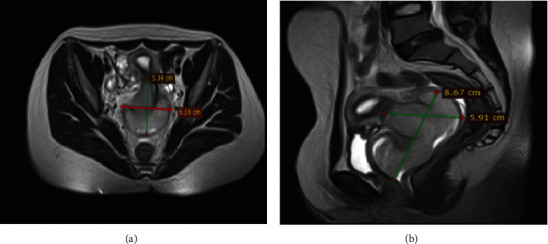

简介原发性对角线外生殖细胞瘤(EGCTs)是一种非常罕见的临床疾病,最常见于男性。在女性中,胎盘、骨盆、子宫、大脑和纵隔是最常见的生殖细胞瘤部位,其组织学主要表现为非生殖细胞瘤。在本报告中,我们介绍了一例年轻女性患者的原发性宫颈胚胎发育不良瘤。病例报告。一名 18 岁的无生育能力女性因 12 个月的阴道出血和分泌物病史前来就诊。血常规检查和血清肿瘤标志物水平均在正常范围内。胸部 X 光检查正常。高分辨率盆腔磁共振成像显示,宫颈阴道肿块轮廓清晰,大小为 8 × 6 × 5 厘米,向阴道口扩展,呈轻度均质对比增强。患者在麻醉状态下经阴道进行了切口活检,组织学检查结果与畸形精原细胞瘤一致。再次复查盆腔磁共振成像显示,肿块缩小了 70% 以上。患者接受了 4 个周期的博来霉素、依托泊苷和顺铂化疗。在获得部分反应后,又进行了盆腔外放射治疗。放疗 3 个月后,对比腹盆腔 CT 扫描显示宫颈阴道肿块复发,并向盆腔侧壁扩展。患者因生殖细胞瘤复发开始接受伊佛酰胺、紫杉醇和顺铂(ITP)二线化疗,但后来死于肾积水、慢性贫血和败血症:结论:子宫颈是原发性生精细胞畸形瘤的一个非常不寻常的部位,其临床病程可能非常凶险。要确诊该病,尤其是对宫颈病变的年轻患者,必须高度怀疑并进行全面检查。

Introduction: Primary extragonadal germ cell tumors (EGCTs) are a very rare clinical encounter most commonly reported in males. Among females, the placenta, pelvis, uterus, brain, and mediastinum are the most common extragonadal sites and predominantly display nondysgerminoma histology. In this report, we present a case of a primary cervical dysgerminoma in a young female patient. Case Report. An 18-year-old nulligravid woman presented with a 12-month history of vaginal bleeding and discharge. Routine blood tests and serum levels of tumor markers were within normal limits. The chest X-ray was normal. A high-resolution pelvic MRI showed a well-defined lobulated cervicovaginal mass measuring 8 × 6 × 5 cm expanding into the vaginal canal with mild homogenous contrast enhancement. An incisional biopsy was performed vaginally under anesthesia, and histologic findings were consistent with dysgerminoma. A repeat follow-up pelvic MRI was done and showed a reduction in the size of the mass by more than 70%. The patient was treated with 4 cycles of bleomycin, etoposide, and cisplatin chemotherapy. Additional external pelvic beam radiation treatment was administered for a partial response. After 3 months of radiotherapy, a contrast abdominopelvic CT scan showed a recurrent cervicovaginal mass with extension to the pelvic sidewalls. The patient was initiated with ifosfamide, paclitaxel, and cisplatin (ITP) as second-line chemotherapy for a recurrent germ cell tumor but later died from hydronephrosis, chronic anemia, and sepsis.